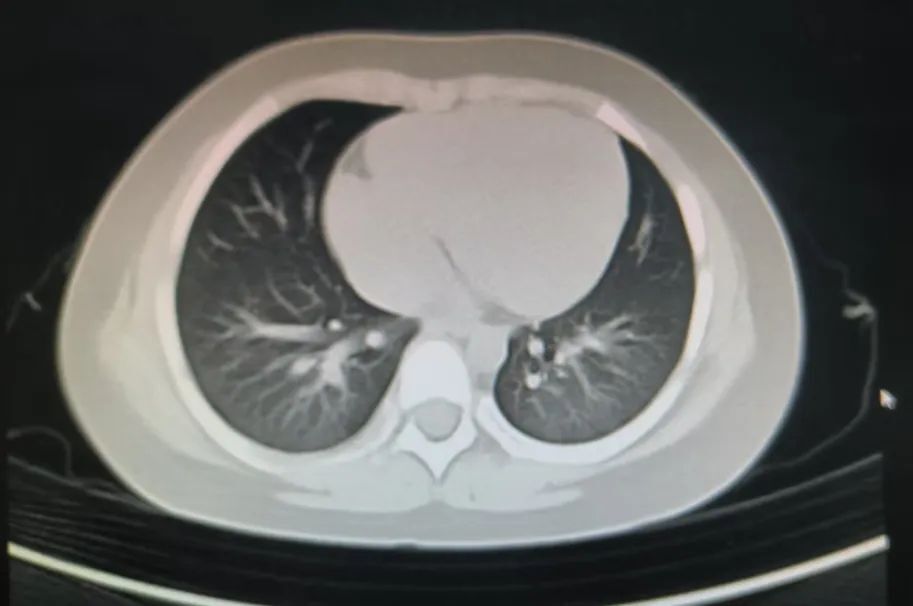

然而,回家没多久,涵涵再度发热、咳嗽,病情出现反复。进一步的 CT 检查确诊为大叶性肺炎,又经过 5 天的精心治疗,病情逐渐好转。可10 天后复查 CT 时,结果却让家长的心又悬了起来:双肺呈现多发斑片密度增高影及磨玻璃阴影。

我们医疗组接过涵涵的 CT 片子,仔细端详,难题却接踵而至。倘若阴影靠近肺外周,借助气管镜下或楔形切除取样进行活检并非难事,可涵涵肺部的阴影呈散分布,位置还很深,若强行实施活检,必然会给孩子稚嫩的肺部造成极大创伤。一时间,这肺部的阴影究竟为何物,我们这些也陷入了困惑。

我们反复比对过往的 CT 结果,同时紧密结合涵涵的体征以及各项检查指标,终于从细微之处捕捉到了关键线索,进而大胆推测:肺部阴影可能是过敏性肺泡炎。

作为主管医生,我将这一判断如实告知了家长,并与他们沟通了激素治疗。令人欣喜的是,激素治疗仅三天,奇迹便如我们所预判的那般出现了。复查片子显示,涵涵肺部的斑片状阴影较之前范围明显缩小,这无疑证实了我们的判断准确无误,孩子患的正是过敏性肺泡炎。然而,新的问题接踵而至,究竟是什么引发了过敏?在对涵涵进行激素规范化治疗的同时,找出并脱离过敏原也至关重要。为此,我们多次与家长深入交流,逐一排查真菌、细菌、动植物蛋白类抗原等各类可能的过敏因素,可遗憾的是,过敏原始终如一团迷雾,隐匿不见。住院一周后,考虑到病情相对稳定,我们安排涵涵出院,并反复叮嘱家长务必遵医嘱服药,定期复查 CT。

2025 年 1 月,我像往常一样在门诊坐诊,涵涵在家人的陪同下来院复诊,拍摄CT影像结果令人振奋:双肺上散在的斑片状阴影已然完全吸收。